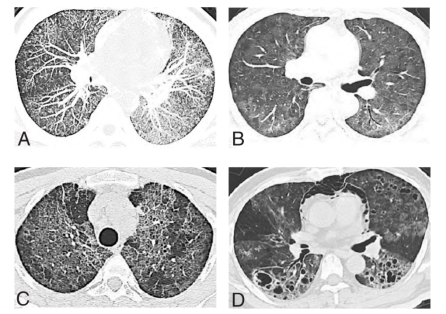

(2)影像学检查:典型影像学表现包括:粟粒结节、磨玻璃影、“碎石路”征、肺气囊、纵隔气胸(图1)。在早期呈弥漫性肺泡和间质浸润性阴影,迅速融合而成为广泛肺实变,可见支气管充气征,一般不累及肺尖、肺底和肺外带。

图1. 耶氏肺孢子菌肺炎不同时期肺部CT影像(A粟粒结节;B磨玻璃阴影;C“碎石路”征;D肺气囊、纵隔气肿)